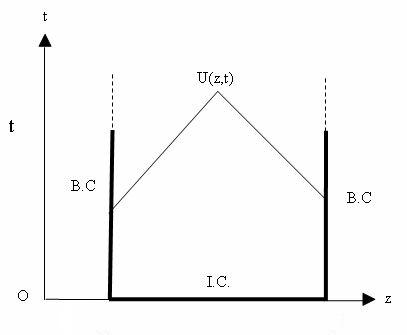

Boundary conditions from multiscale modeling of circulation: Another approach to impose the boundary conditions is to use reduced models, as 1D model or 0D (lumped) models. 1D and 0D models are mathematical models able to reproduce the systemic and pulmonary circulation. Figure 10 shows a standard approach to provide realistic local boundary conditions for 3D CFD simulations at the specific arterial domain using 1D models of the entire arterial tree and 0D models at the distal ends[83]. 1D model solves the Navier-Stokes equations under some assumptions (see appendix 9) and lumped models (0D models) can be derived from electrical circuit analogies where blood flow is represented by the current and arterial pressure by the voltage. Usually the electrical components of these circuits are resistances, inductances and capacitors. Where resistances represent arterial and peripheral resistance that occur as a result of viscous dissipation inside the vessels, capacitors represent volume compliance of the vessels that allows them to store large amounts of blood, and inductors represent inertia of the blood[75]. The values of these electrical components can be estimated from physical data of the subject [84][85]. This approach is quite used because it is capable to account for the effect of local pathological conditions on the whole circulatory system, providing realistic boundary conditions for the 3D problem [75][79][86].

| Figure 10: Coupling of 0D heart model, with 1D model (Systemic Circulation), 3D model (patient-specific geometry) and 0D lumped models (terminal resistance) to perform a computational analysis |